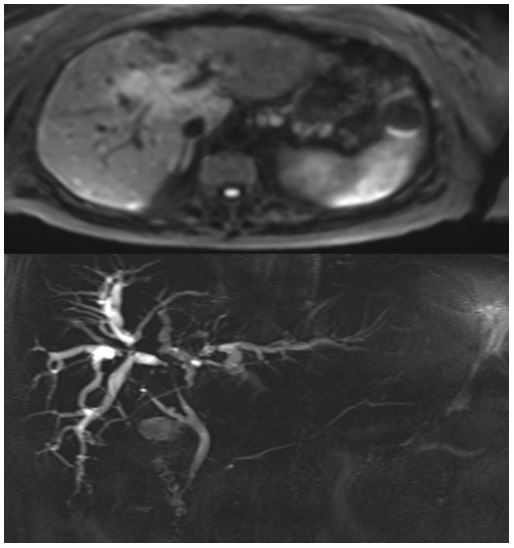

Computed tomography of the chest and abdomen disclosed pathological contrast and wall thickening of the proximal bile duct and right hepatic duct. The left hepatic duct was no longer visible due to diffuse tumor infiltration of the central hepatic parenchyma resulting in dilatation of the intrahepatic bile ducts. A complete occlusion of the biliary convergence with complete separation of the bile ducts to the 2nd convergence was observed. In addition, multiple adenopathy of the hepatic hilum, celiac, gastric greater curvature and retroperitoneal and cardio-phrenic were visible (Figure 1). Magnetic resonance imaging confirmed the CT findings with additional intrahepatic, vertebral body metastases and multiple pulmonary nodules (Figure 2).

Figure 2: Abdominal MRI.